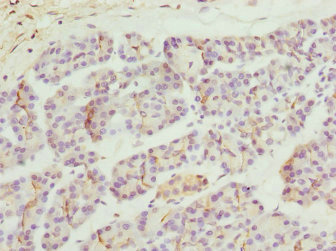

Immunohistochemistry of paraffin-embedded human pancreatic tissue using CSB-PA064019ESR2HU at dilution of 1:100